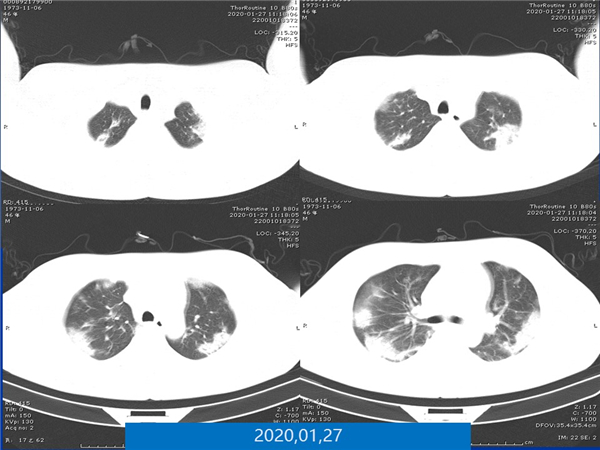

【病例分享】新型冠狀病毒感染肺部CT影像4例(常德市第一人民醫(yī)院)